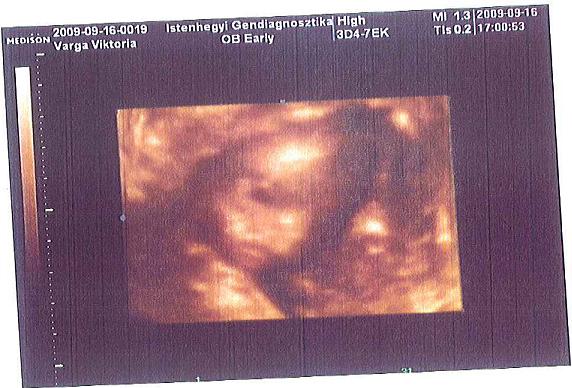

és a doktorbácsi azt mondta, hogy június 6.-án fogant

Úgyhogy nálunk pikk pakk mentek a dolgok